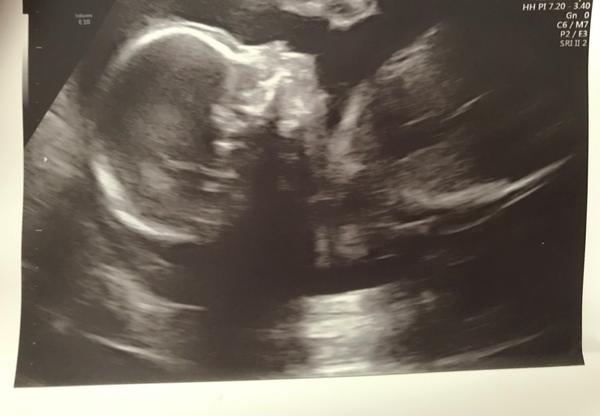

Tak nam na utz ve 21.tt rekli, ze ma mala malou ustupujici bradicku, ale ze se nejedna o zadnou vadu pry, ze nam vysly vsechny testy dobre a ze holt bude mit malou bradu. Prikladam foto z utz, me proste prijde ze tam ani nepoznam pusinku a tu bradicku no.. Jsem z toho docela na nervy...

@bramarfi To je prave to - ze u vas to nebylo ani poznat na utz, ale kdyz si toho u nas i vsimli? Koukala na to jedna mudr a ta si pak jeste zavolala jednoho mudr na konzultaci k tomu. Zkoumali to oba dlouho a rekli, ze holt kazdy jsme nejaky.. Ale z te fotky moudra nejsem.. tak snad jim muzeme verit.